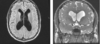

identify

multiple sclerosis

plaque (lesions) perpendicular from lateral ventricles